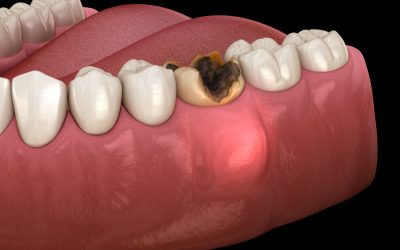

Ascesso dentale: cosa sono l’apicale e il parodontale

Esistono diverse tipologie di ascesso dentale, tra cui i più comuni sono l’ascesso apicale e quello parodontale. Il primo si forma all’estremità della radice del dente ed è spesso causato da una carie, mentre il secondo interessa la gengiva vicino alla radice ed è legato a un’infezione parodontale.